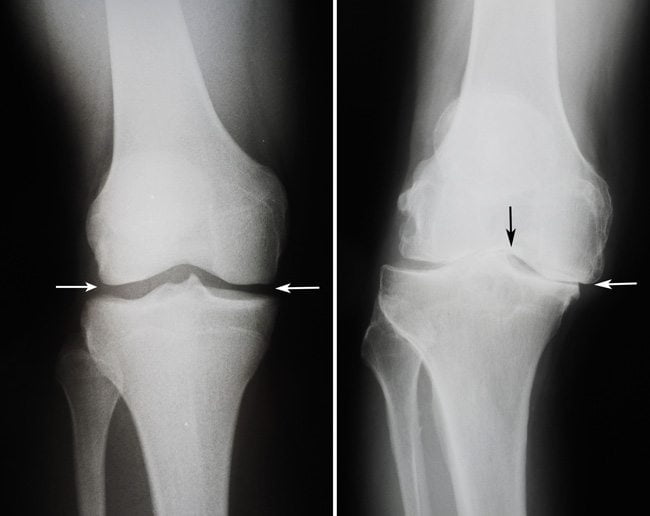

- рентгенография. Информативна при переломах костей, хронических артритах, остеоартрозе и т. д. Дает возможность выявить нарушение целостности или очаги деструкции в костях, формирующих коленный сустав;